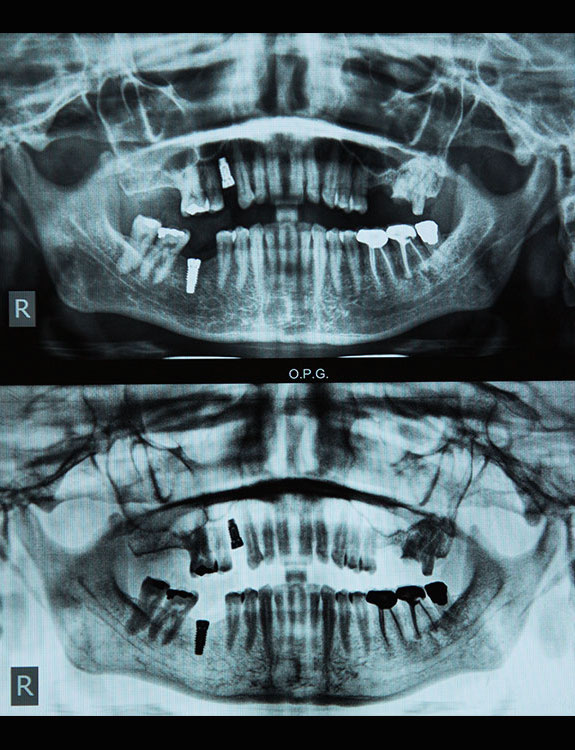

Dental implants are artificial tooth roots made of medical-grade titanium that are surgically placed into the jawbone. Once the implant integrates with the bone, a crown is fixed on top, giving you a strong, natural-looking replacement tooth.

At Dental Que, implant dentistry combines clinical expertise with patient-centric care. Your treatment is led by our experienced implantologists: Dr Sumit Dutta & Dr Harsha Dutta

Both doctors are highly skilled Implantologists in Punjabi Bagh, known for their precise planning and ethical approach to implant care.